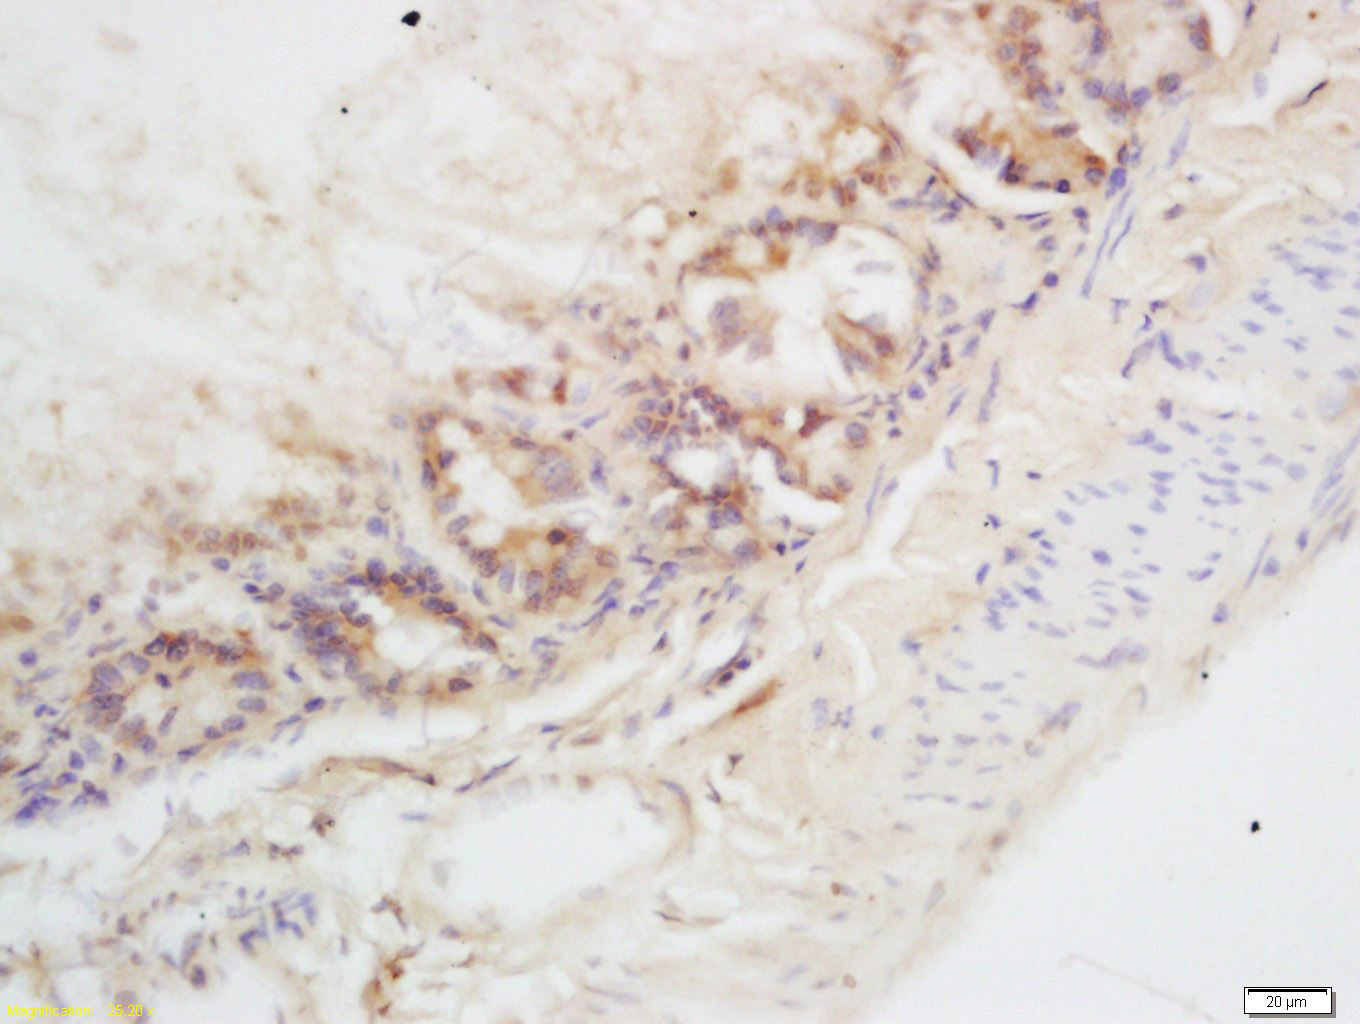

Tissue/cell: mouse intestine tissue; 4% Paraformaldehyde-fixed and paraffin-embedded; Antigen retrieval: citrate buffer ( 0.01M, pH 6.0 ), Boiling bathing for 15min; Block endogenous peroxidase by 3% Hydrogen peroxide for 30min; Blocking buffer (normal goat serum,C-0005) at 37℃ for 20 min; Incubation: Anti-CHKL Polyclonal Antibody, Unconjugated(bs-10935R) 1:200, overnight at 4°C, followed by conjugation to the secondary antibody(SP-0023) and DAB(C-0010) staining